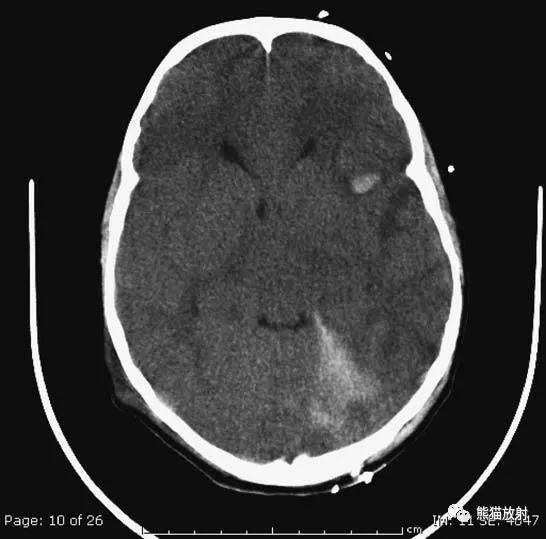

▲动脉瘤破裂导致蛛网膜下腔出血、

脑室积血、非交通性脑积水

与外伤性蛛网膜下腔出血不同,动脉瘤破裂导致的SAH常不累及大脑凸面,而位于基底池附近。脑动脉瘤常位于鞍上池的Willis环血管。

A:四脑室积血;

B:中脑导水管、环池、右侧侧脑室颞角积血,前交通动脉处(动脉瘤好发位置)出血密度较高;

C:三脑室积血;

D-F:侧脑室积血,蛛网膜下腔出血(血液代替了脑脊液)。